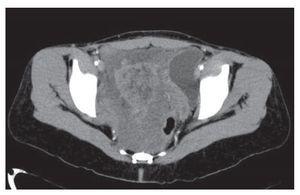

Mujer de 41 años de edad, sin antecedentes, que consultó por historia de dolor pélvico difuso, de baja intensidad, no irradiado, de ocho meses de evolución. Al examen físico se encontró una masa adherida a planos profundos y poco dolorosa a la palpación. Se le realizó una tomografía computadorizada que informó una extensa neoplasia pélvica de características malignas, que se extendía hasta el espacio isquiorectal, con desplazamiento y compresión de la vejiga y el útero, además de escaso líquido alrededor de la lesión (Figura 1). Se realizó una resonancia magnética nuclear que demostró una lesión de 14 x 14 cm, posiblemente de origen lipomatoso con degeneración mixoideangiolipomatosa, con probable infiltración al recto y sigmoides, dilatación pielo-ureteral bilateral por obstrucción del tercio distal de los uréteres (Figuras 2 y 3). Se realizó una colonoscopia que sólo evidenció desplazamiento del sigmoides por compresión extrínseca. Se le realizó una laparotomía exploratoria encontrando una masa pélvica de 15 x 20 cm, la cual se pudo separar de las estructuras adyacentes y resecar en su totalidad. El reporte histopatológico fue de una masa de 15 x 18 cm, con un peso de 260 g, de color amarillo-gris liso y opaco, de aspecto nodular y consistencia blanda. Al corte se encontraron áreas quísticas compatibles con angiomixoma (Figura 4). La paciente presentó una evolución satisfactoria, se le dio egreso. Actualmente se encuentra asintomática y sin datos de recurrencia.

Figura 2. Tomografía computadorizada que mostró masa con infiltración al recto sigmoides con obstrucción ureteral bilateral